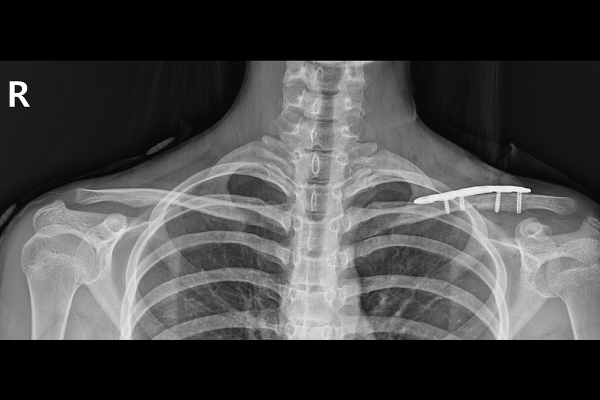

b72968fc2915dd5bd436116d60cd6556_1767918764_739.png

금속판을 이용하여 고정해줍니다.

수술 후 X-RAY를 보면 골절되었던 쇄골뼈가 금속판으로 정확한 위치에 잘 고정되어 있음을 확인할 수 있습니다.